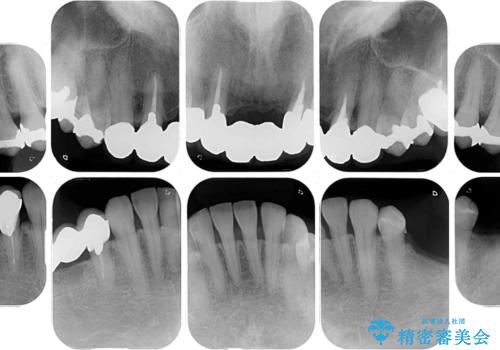

- 口の中に気になるところが沢山あるものの、地元ではなかなか治療を行ってくれるところがないとのことで、沖縄県の離島より来院された患者様です。

金属を使用した前歯のブリッジや奥歯の銀歯は全てオールセラミッククラウンまたはセラミックインレーとし、左下の奥歯はインプラントにより治療を行うこととしました。

外科処置を行うため、治癒を待つ期間が数ヶ月あるため、その期間を利用して下顎前歯のスペースを矯正治療で閉じることとしました。